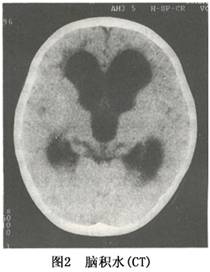

CT或MRI可確定腦室擴大及程度及皮質萎縮的程度,有時可同時瞭解引起腦積水的原因(圖1,2)。此外,CT或MRI還能瞭解腦積水是急性腦積水還是慢性腦積水,爲臨牀處理措施的應用提供依據。在腦積水的診斷中,應注意與腦萎縮引起的腦室擴大相區別,後者腦室擴大的同時可明顯地顯示出側裂或腦溝,甚至可有腦溝及腦裂的明顯擴大。另外診斷腦積水應儘可能明確是梗阻性腦積水還是交通性腦積水。